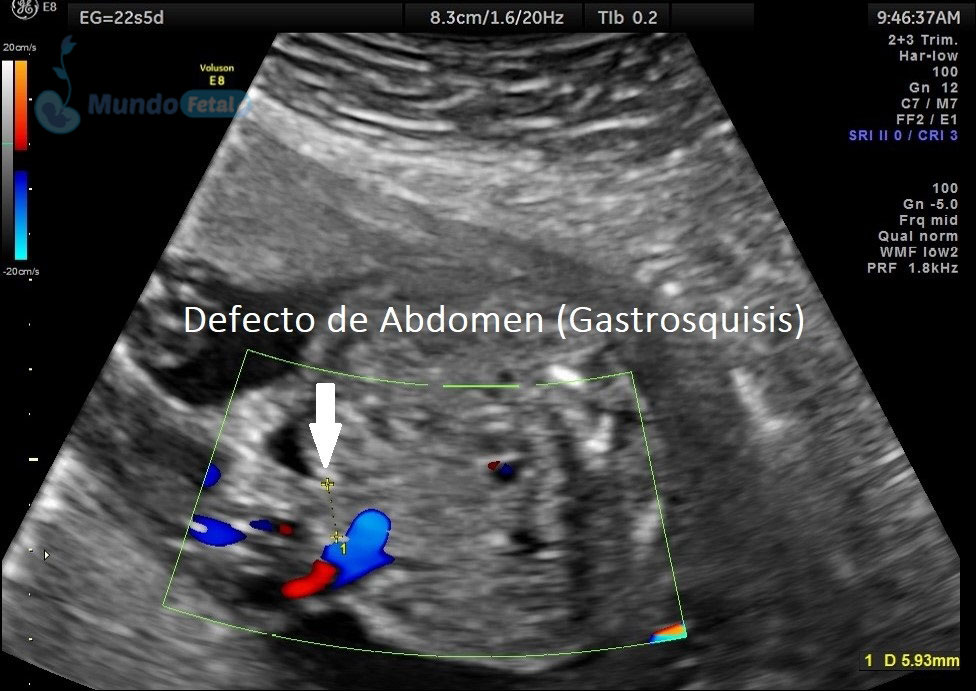

Estudio llevado a cabo en todo bebe, en quien se haya detectado alguna alteración anatómica o marcador de riesgo, valorando todos sus órganos, aparatos y sistemas, de manera específica y detallada.